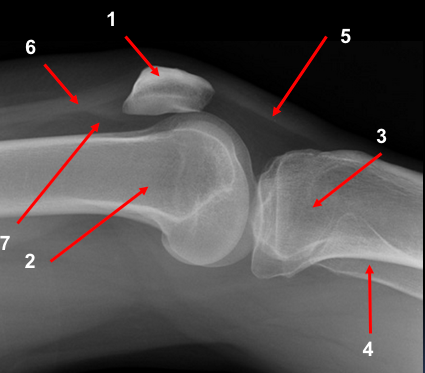

A 30 year old man presented to the ED with left knee pain after a cycling accident.

On examination there was no deformity, but it was painful for him to weight-bear. Movements of his knee were painful, and this limited his movements.

What is a lipohemarthrosis?

Results from an intra-articular fracture with escape of fat and blood from the bone marrow into the joint, and is most frequently seen in the knee.

What normal variant can be seen in this image?